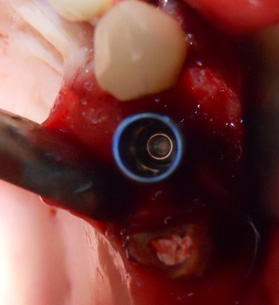

Presentazione del caso:

Inserimento in impianto MIS Seven 3,75x11,5 in zona 24 previa osteoplastica

(Intervento e foto eseguiti da me in 40min )